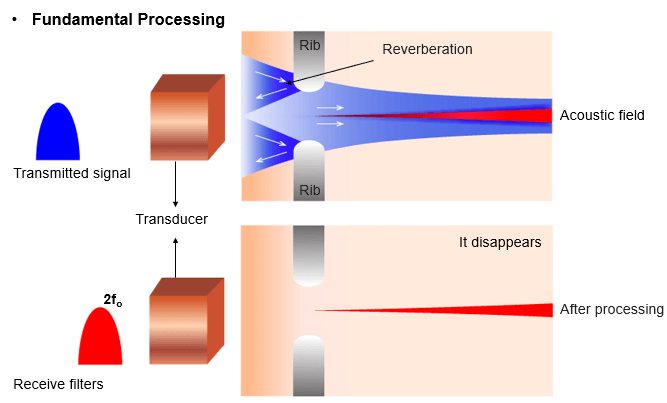

Tissue Aberrations

Harmonic imaging is also used for aberration corrections. Aberration phenomenon occurs when the ultrasonic waves are distorted due to local changes in the speed of sound. Shallow fat and skin layers distort sound beam. It is important to know that distortions are of low energy but send sound in random directions.

As aberrations are also of low energy, they never develop harmonics. Therefore receiver filters tuned at harmonic frequency remove aberrations at f0 and clean up the image.